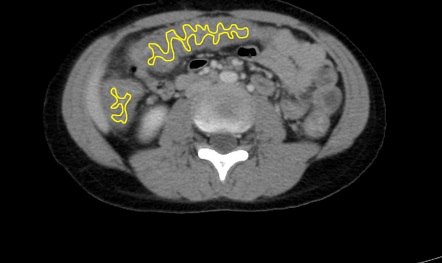

панколит и доппобачееня